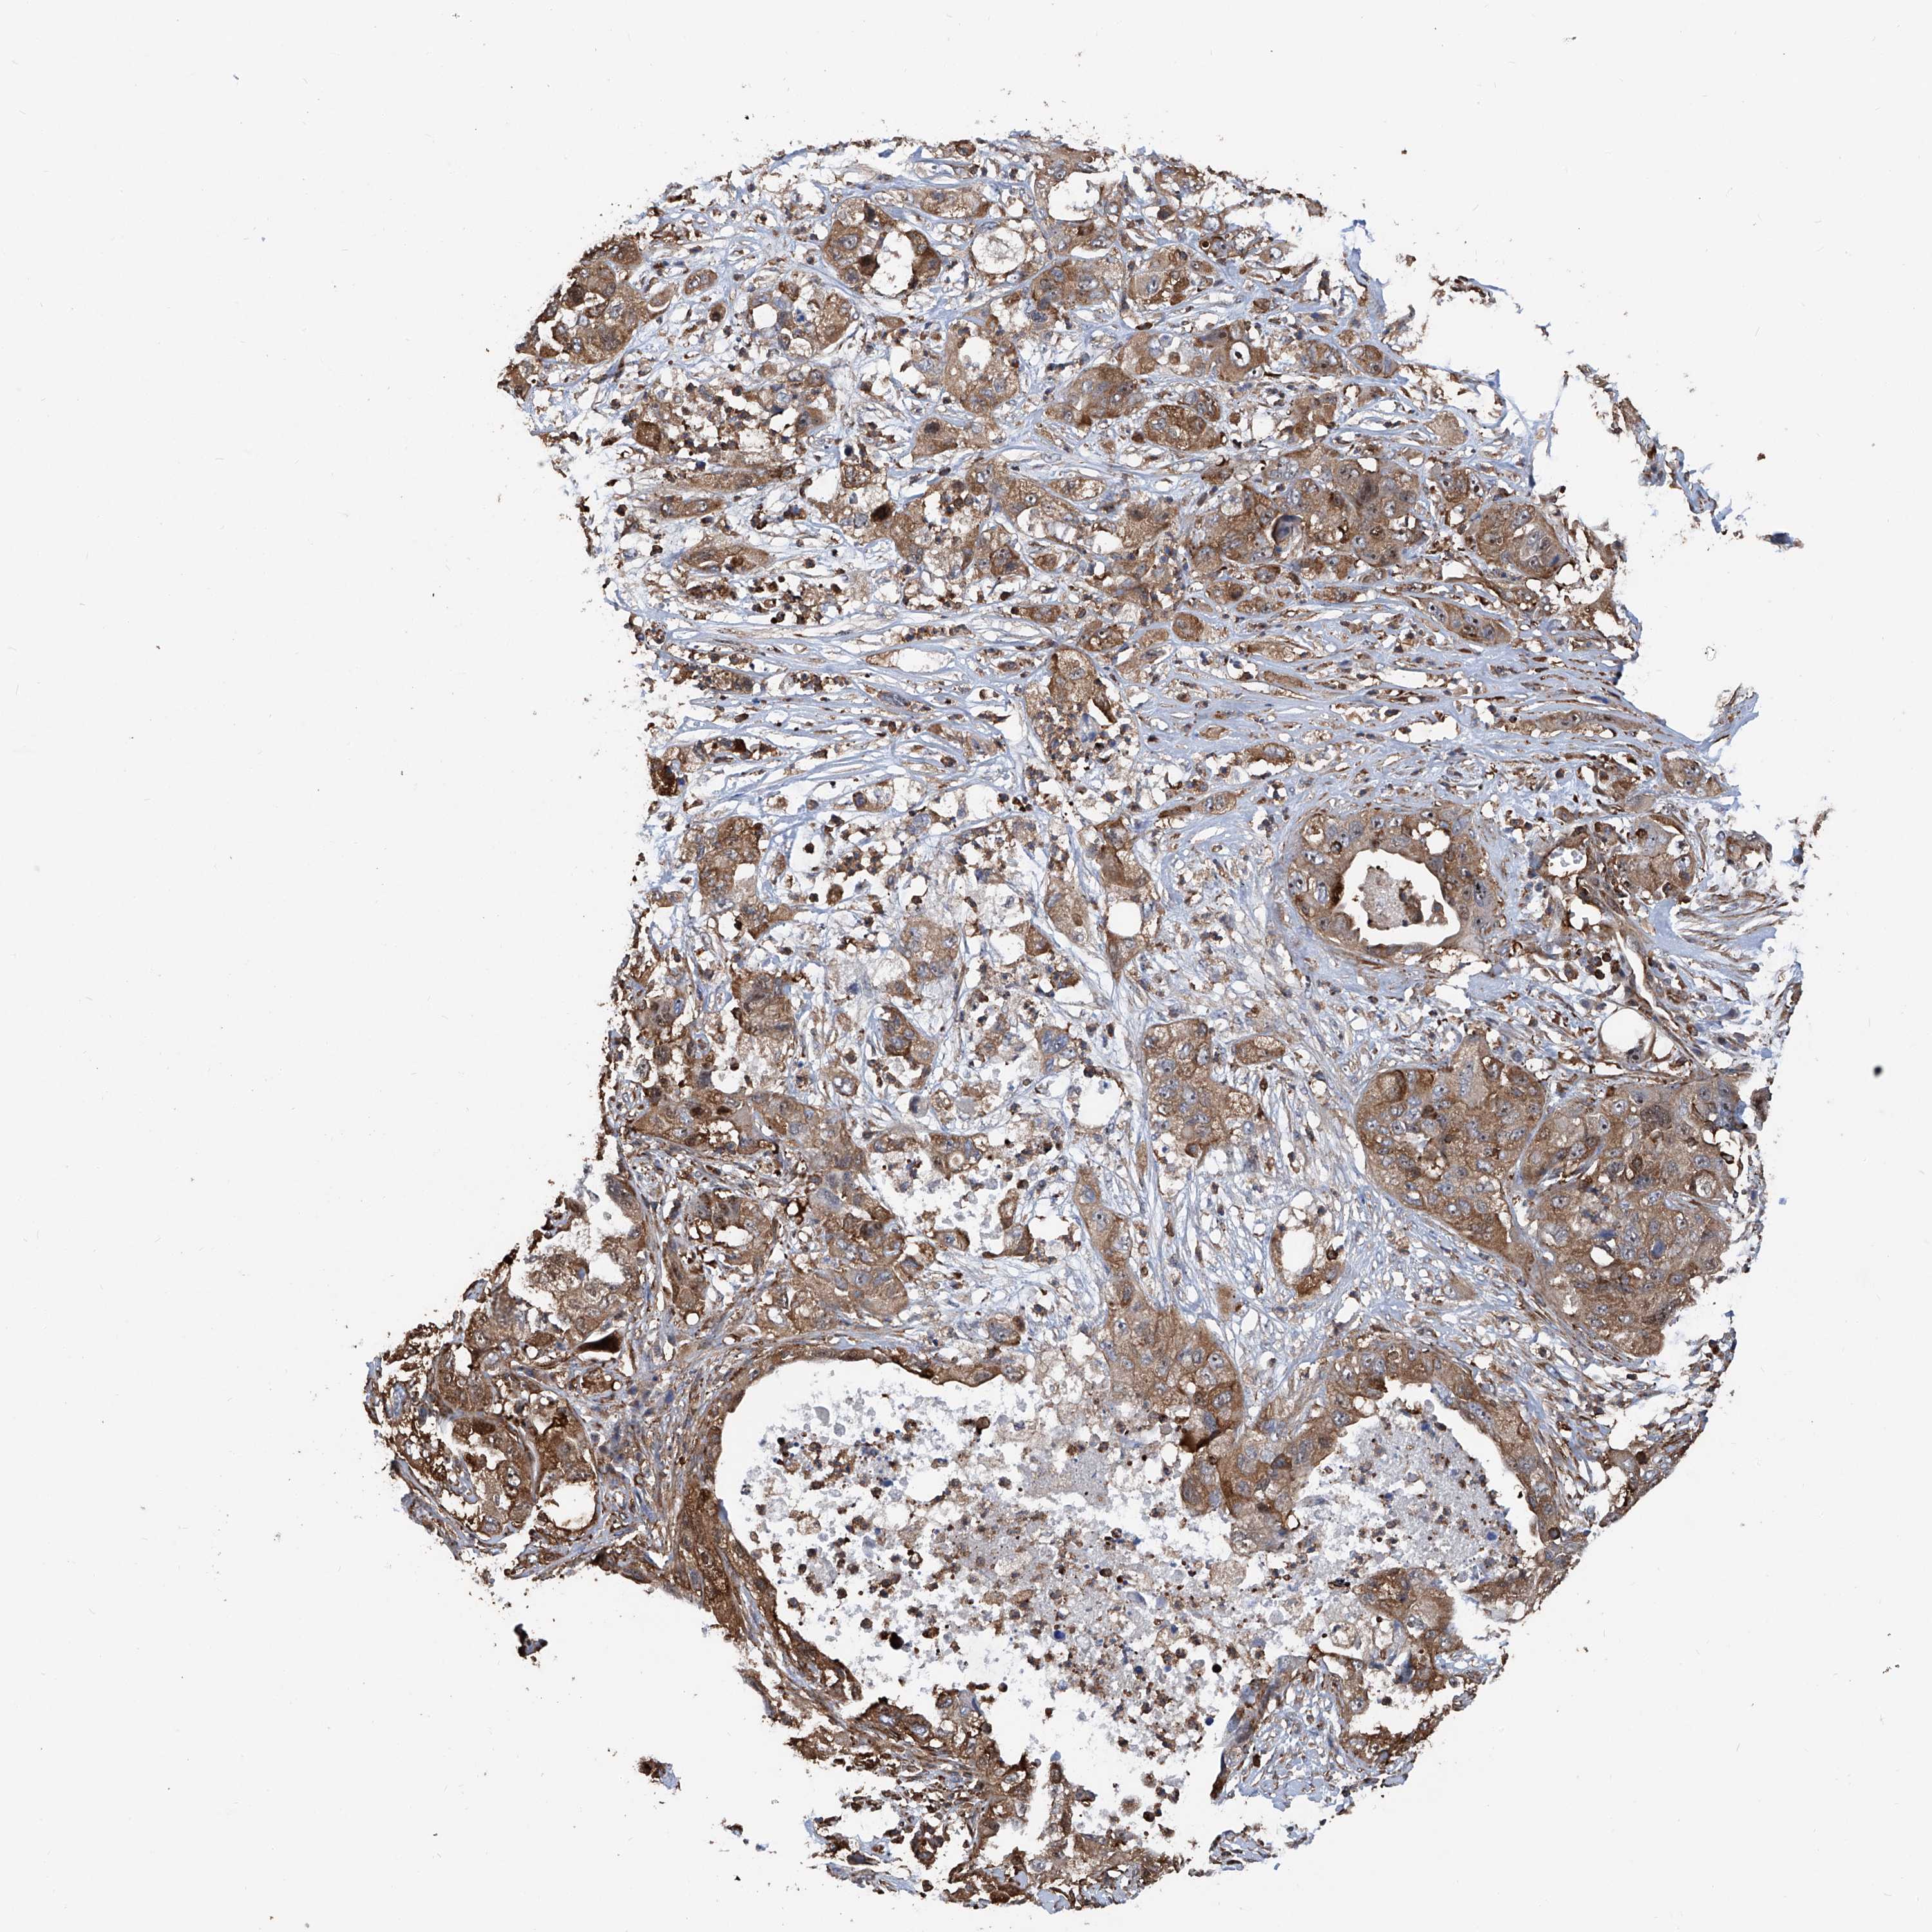

PANCREATIC CANCER - Protein expressioni

A mouse-over function shows sample information and annotation data. Click on an image to view it in a full screen mode. Samples can be filtered based on level of antibody staining by selecting one or several of the following categories: high, medium, low and not detected. The assay and annotation is described here.

Note that samples used for immunohistochemistry by the Human Protein Atlas do not correspond to samples in the TCGA dataset.

Antibody stainingi

Antibody staining in the annotated cell types in the current human tissue is reported as not detected, low, medium, or high, based on conventional immunohistochemistry profiling in selected tissues. This score is based on the combination of the staining intensity and fraction of stained cells.

Each image is clickable and will lead to virtual microscopy that enables deeper exploration of all samples and also displays staining intensity scores, fraction scores and subcellular localization as well as patient and tissue information for each sample.

Antibody HPA028973

Staining

High

Medium

Low

Not detected

Intensity

Strong

Moderate

Weak

Negative

Quantity

>75%

75%-25%

<25%

None

Location

Nuclear

Cytoplasmic/membranous

Cytoplasmic/membranous,nuclear

Adenocarcinoma, NOS